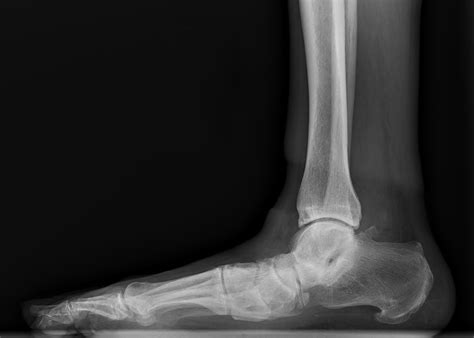

A Simple Guide To What Is Flatfoot Called For New Patients